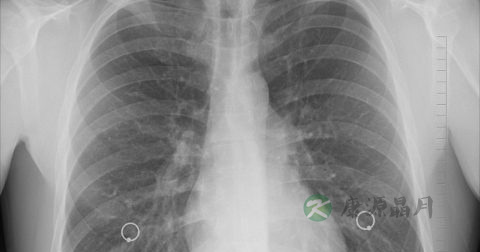

继发于肺部感染的急性脓胸往往是在肺部感染症状好转以后,又再次出现高热、胸痛、呼吸困难、咳嗽、全身乏力、食欲不振等症状,患者常呈急性病容,不能平卧或改变体位时咳嗽,严重时可出现发绀。患侧呼吸运动减弱,肋间隙饱满、增宽,叩患侧呈实音并有叩击痛,如为左侧积液心浊音界不清、如为右侧积液则肺肝界不清,纵隔心脏向健侧移位,气管偏向健侧,听诊患侧呼吸音减弱或消失或呈管性呼吸音,语颤减弱。